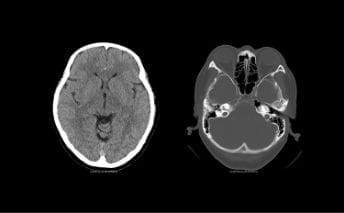

CT(コンピューターX線撮影)

CTはX線を使った人間の身体の透視画像を作ります。カメラが身体の周りをグルグル回り、輪切りの画像を何枚も撮り、単純な断層画像だけでなく、それらをつなぎ合わせて立体的な画像の作成もできます。

- 特長

- X線吸収差の大きい骨や肺の描出に優れている